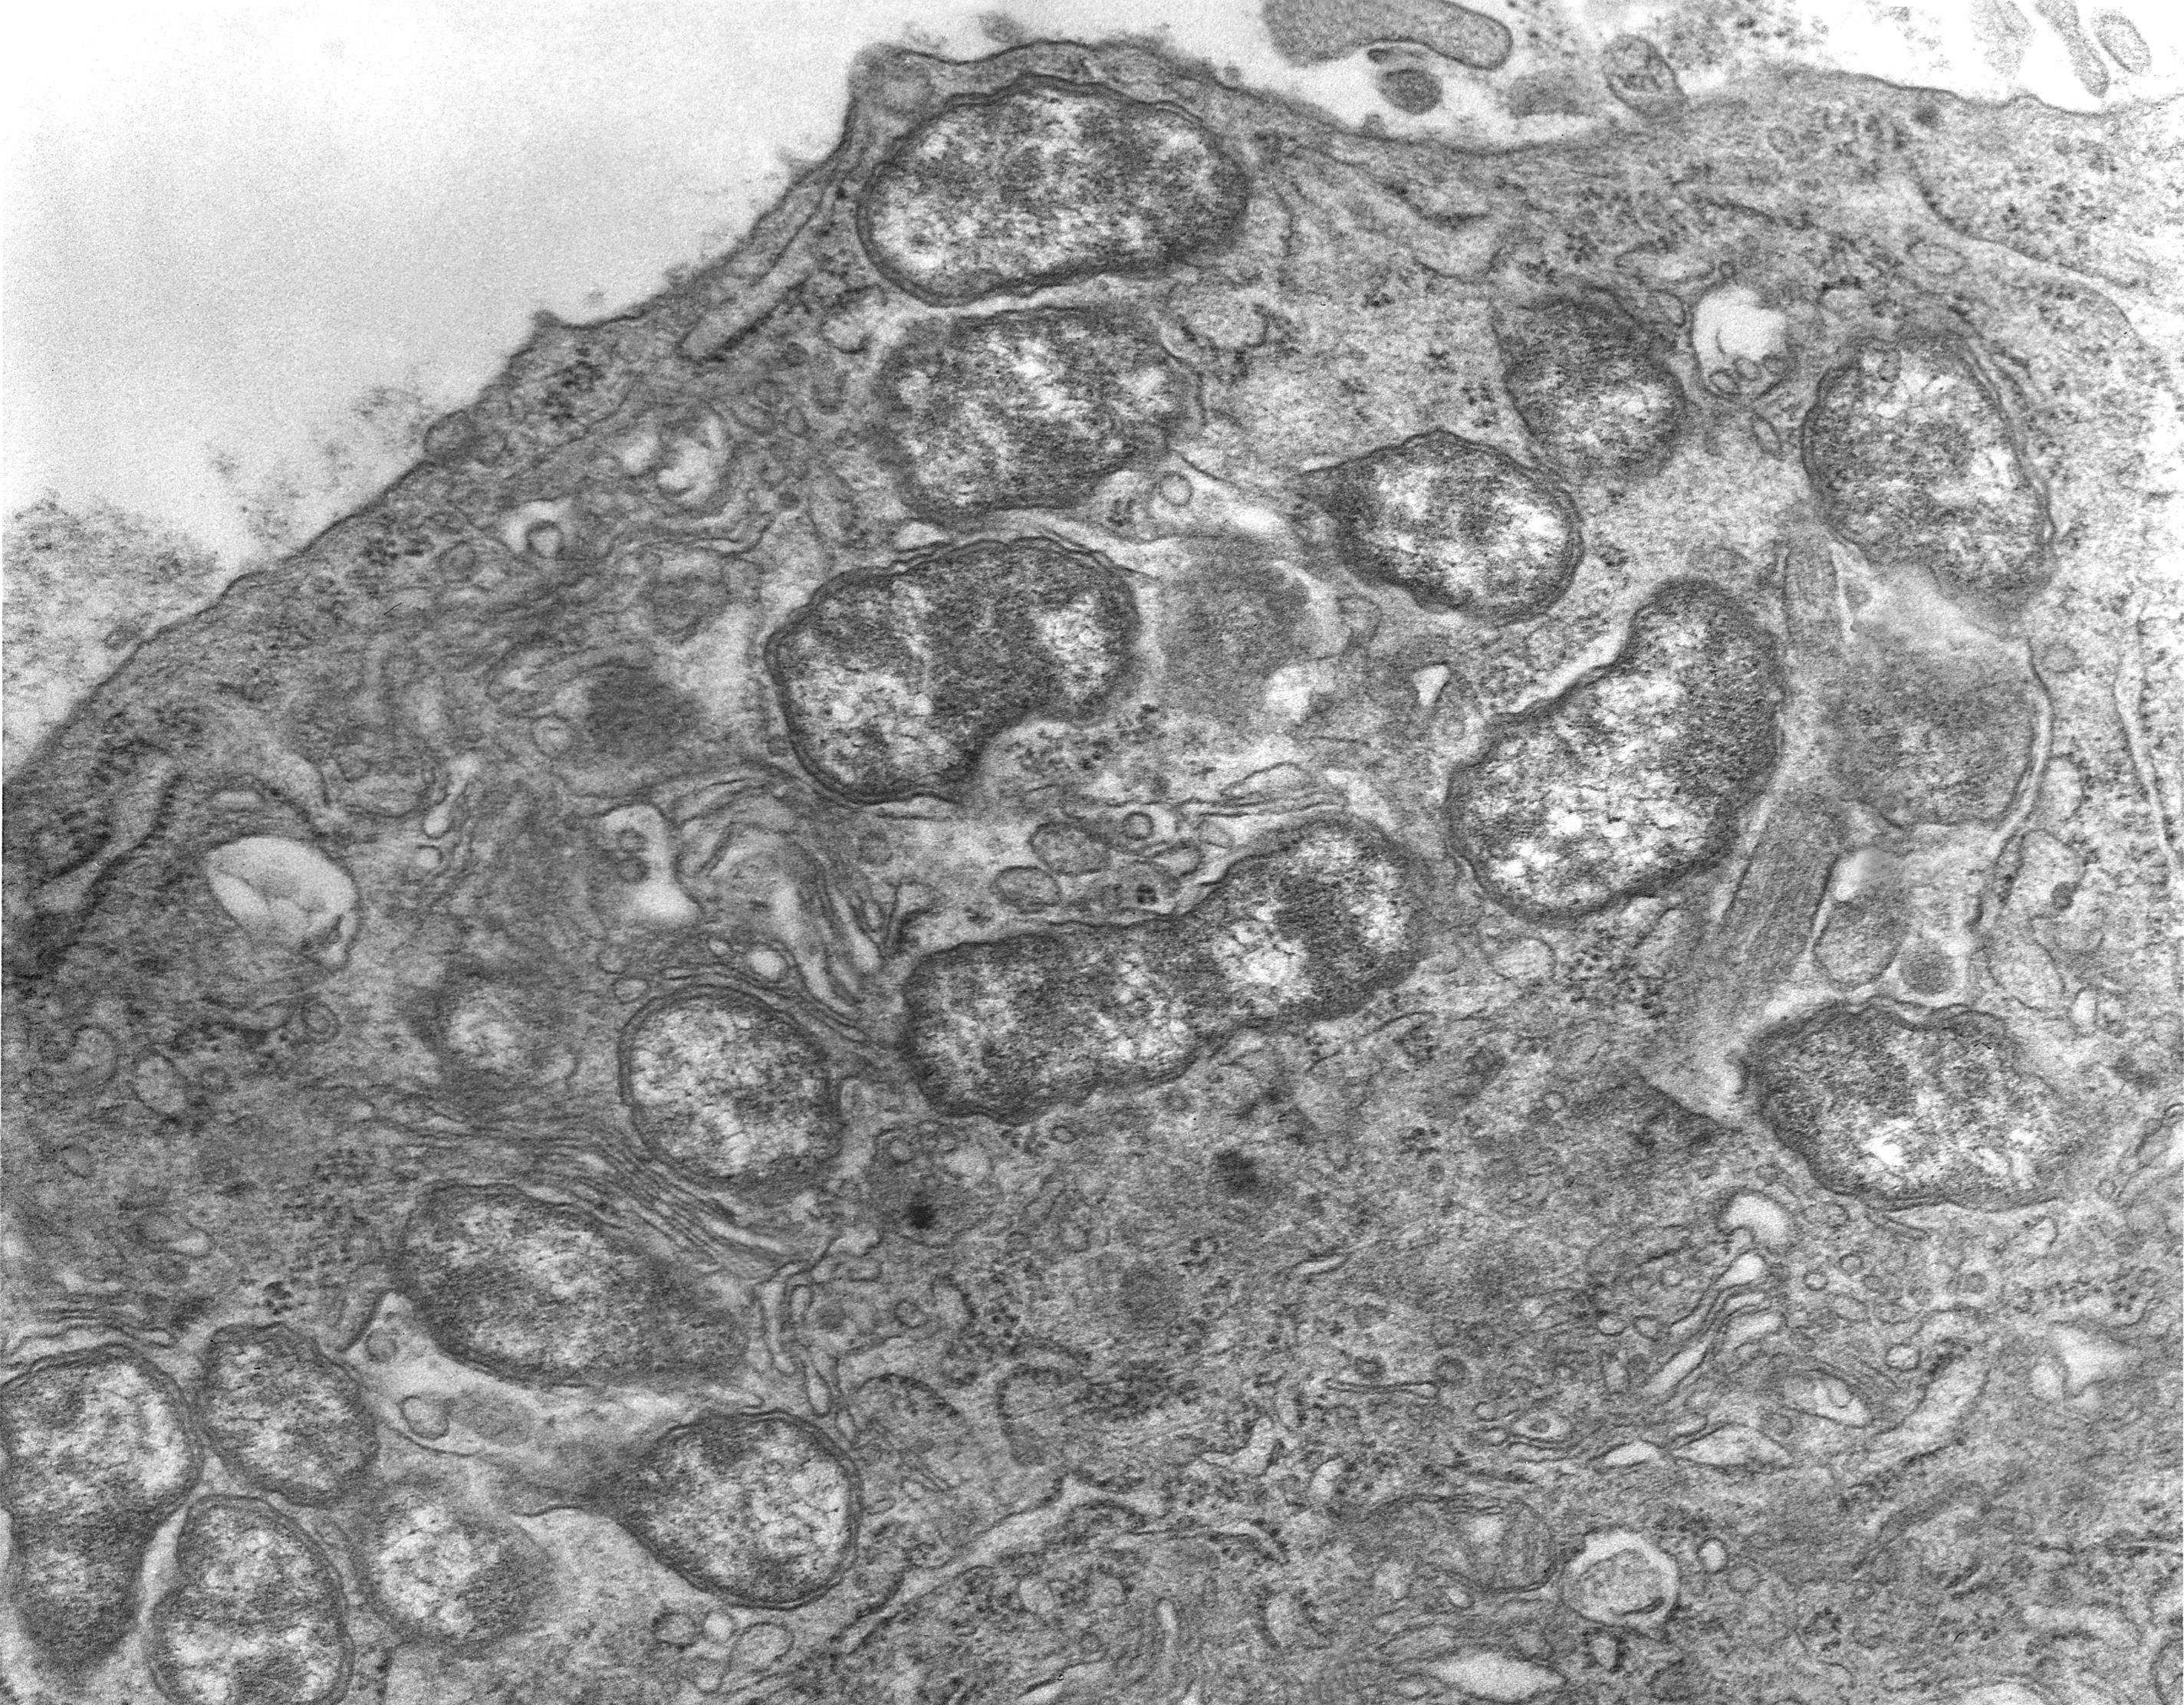

쯔쯔가무시증은 털진드기 유충이 매개하는 감염병으로, 쯔쯔가무시균(Orientia tsutusgamushi)이 원인입니다.

쯔쯔가무시증은 털진드기 유충에 물리면 약 10일 내외의 잠복기를 거친 후 발열, 오한, 두통, 근육통, 발진 등의 증상이 나타납니다.

특히, 물린 부위에는 암적색 반점이 나타나며, 일주일 정도 지나면 이 반점이 팔과 다리 등으로 퍼져나갔다가 자연스럽게 사라지는 것이 특징입니다. 감염자의 피부에는 가피(딱지)라는 독특한 증상이 발생하기도 하며, 이는 진드기가 물린 자리에 형성됩니다.